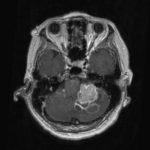

679

'25年10月

30代

聴神経腫瘍

頭蓋内腫瘍摘出術